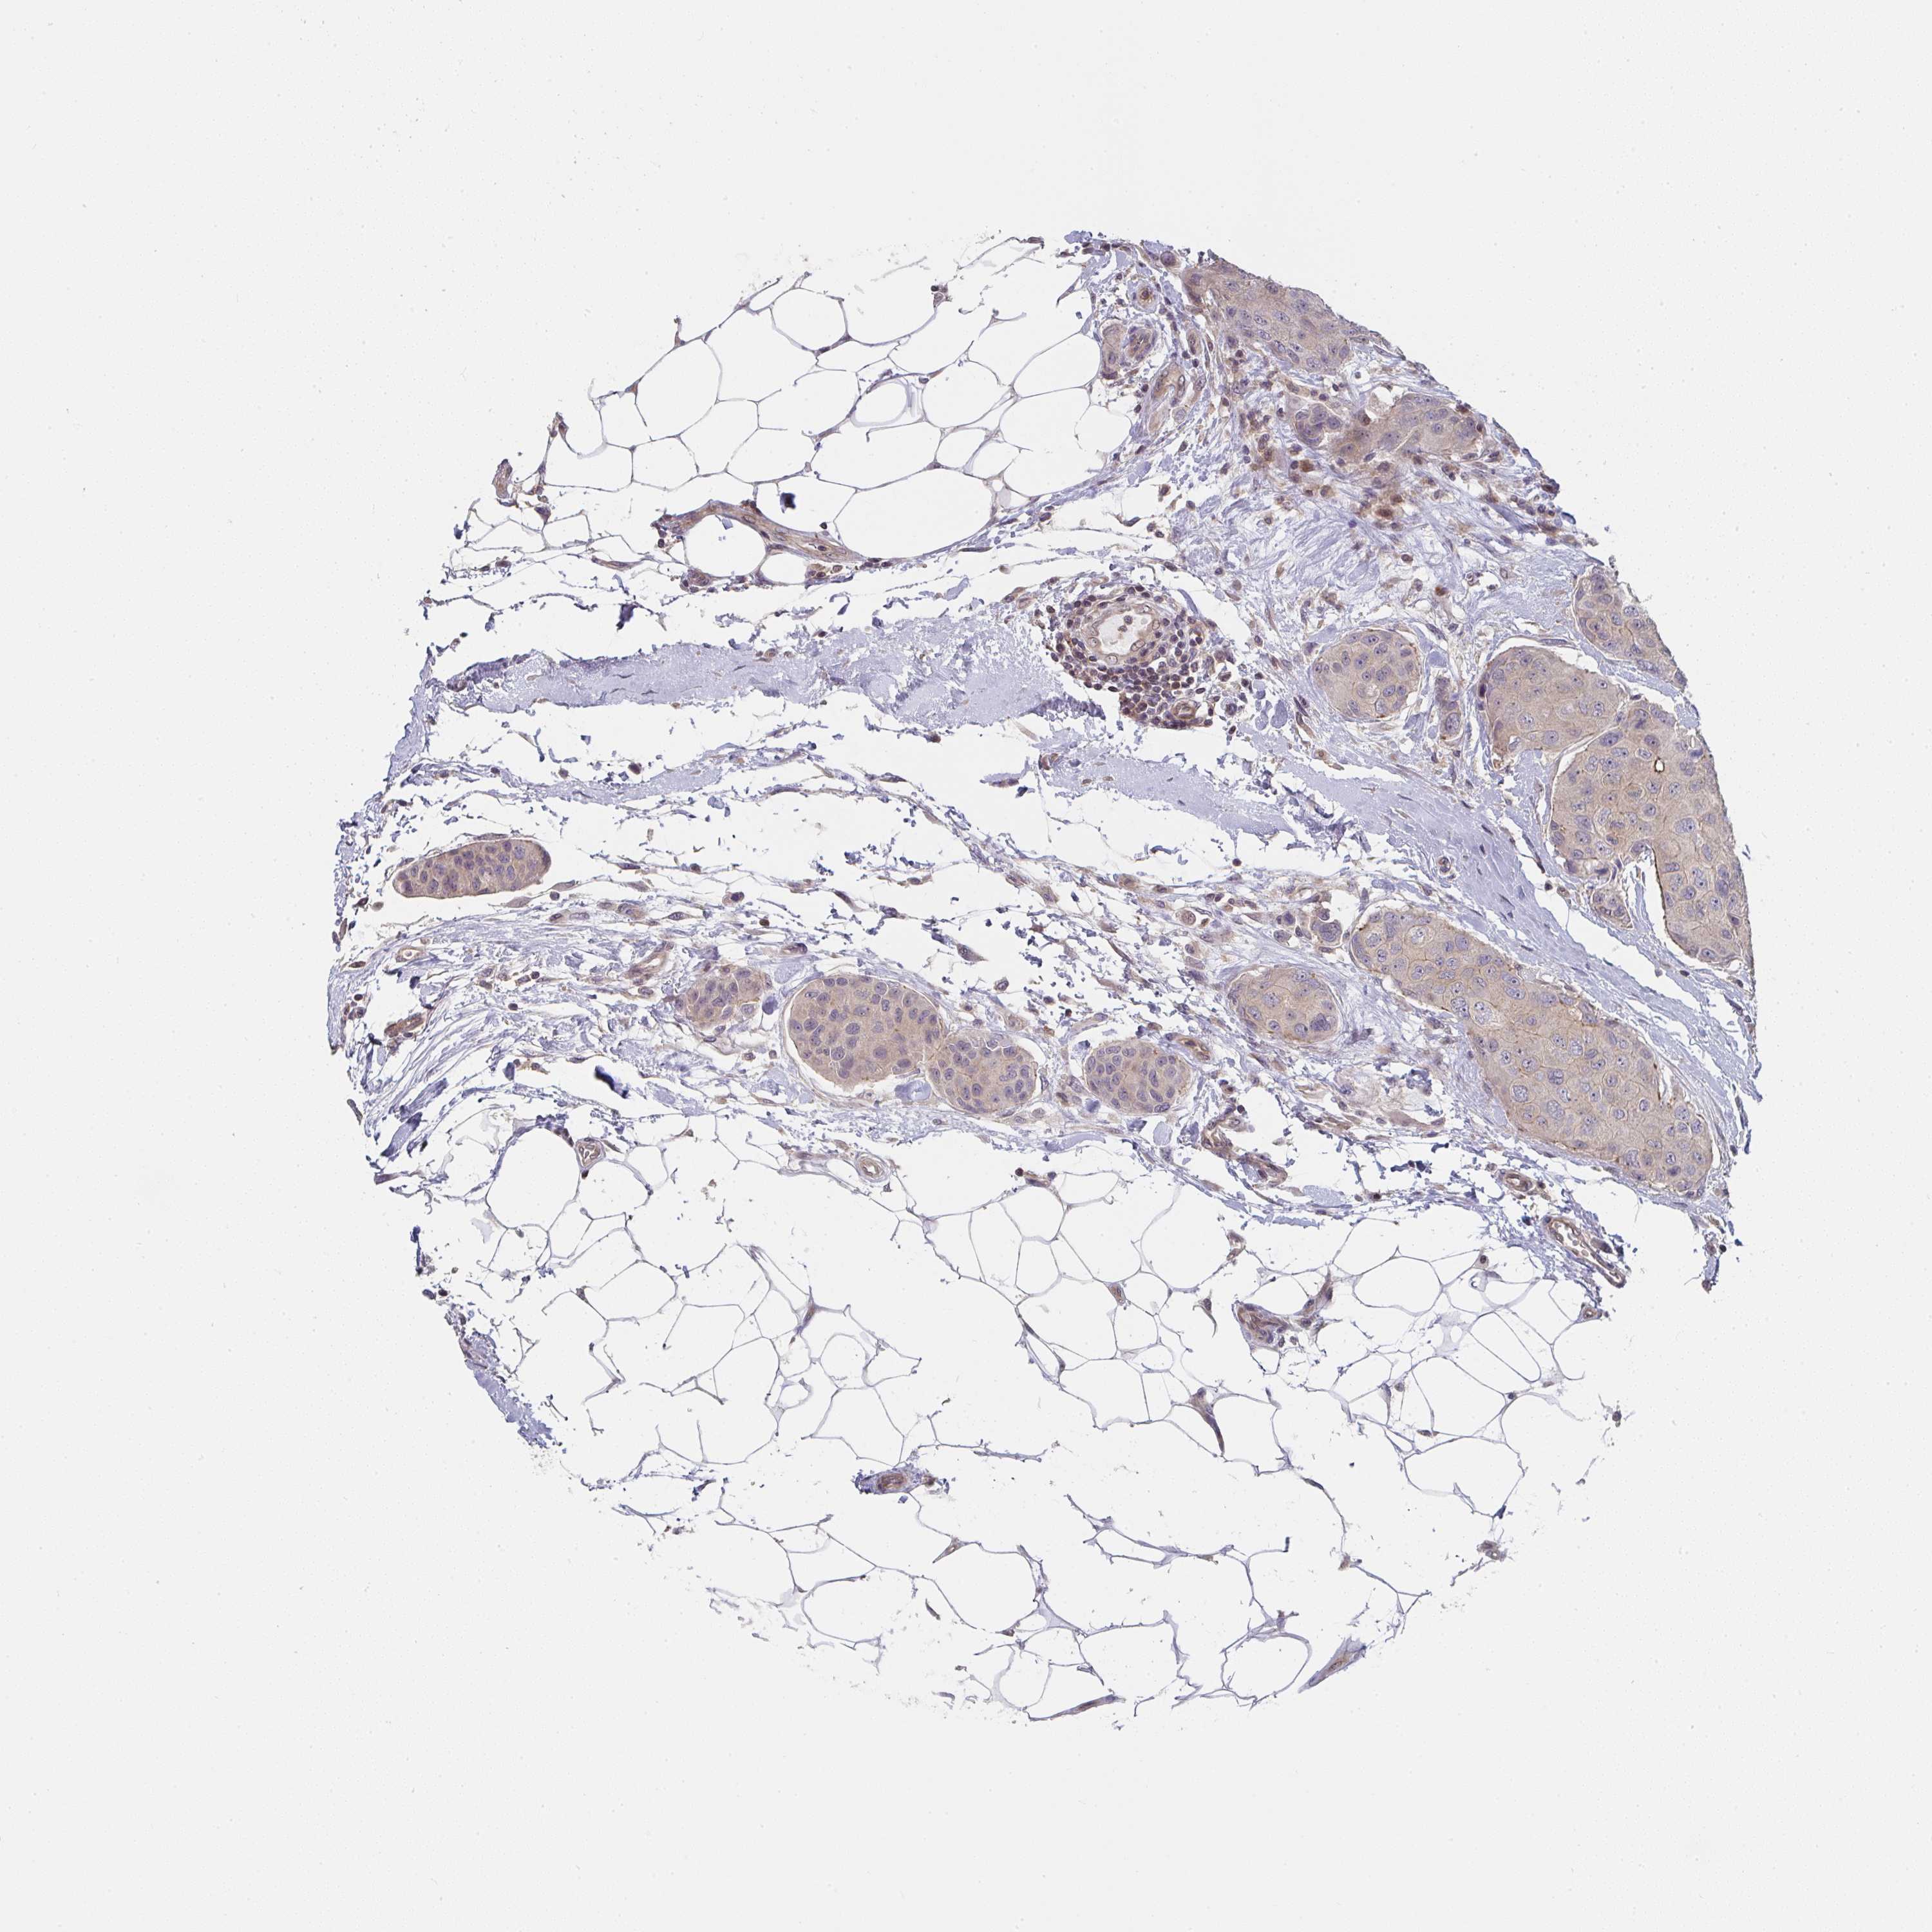

CANCER BREAST CANCER Show tissue menu

BRCA TCGA BRCA VALIDATION PROTEIN EXPRESSION

Breast cancer

Human cancer